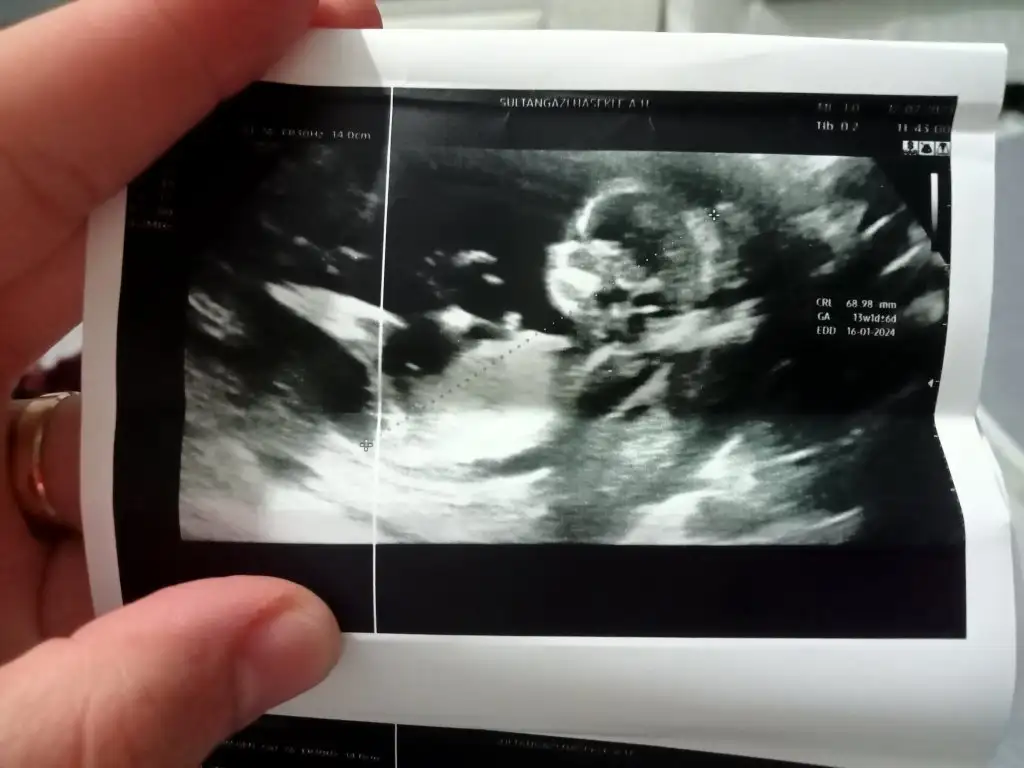

Banada tahminde bulunur musunuz lutfen 12+4 karından ultrasyon

16939936298637089910527887211289.webp

16939936891865931306224271229345.webp